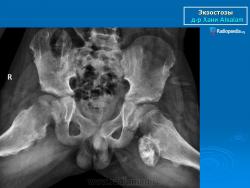

Остеохондрома (син. экзостоз) - это опухолевидное поражение в виде выроста костной ткани, покрытого «шапочкой» из хряща. Аналогичное образование, остеофит, по своему патогенезу не имеет ничего общего с остеохондромой и появляется при остеоартрите вблизи пораженного сустава. Следовательно, термины «остеохондрома» и «остеофит» нельзя использовать как синонимы. Большая часть больных остеохондромой находятся в возрасте до 20 лет. Многие ортопеды считают, что это порок развития, растущий синхронно с эпифизарной пластинкой в течение первых 20 лет жизни. Одним из факторов, вызывающих остеохондрому, является ионизирующая радиация. Показано, что эта опухоль развивается у 12 % больных, получавших в детстве лучевую терапию в дозе 1000-6000 рад. Чувствительными к облучению являются не только эпифизы длинных трубчатых костей, но и зоны роста в костях позвоночника и таза. Период развития пострадиационной остеохондромы, которая бывает множественной, варьирует от 17 мес до 16 лет. Истинная частота находок одиночного новообразования неизвестна, поскольку очень часто при его наличии больные жалоб не предъявляют, и остеохондрома обнаруживается на рентгенограмме лишь как случайная находка. В других случаях пациенты ощущают рост узла и боль. У некоторых из них развивается болезненный спонтанный инфаркт или перелом кости. На боль жалуются и тс больные, у которых над остеохондромой формируются сумки, в просвете которых имеются хрящевые тельца. При увеличении объема такой сумки надлежит проводить дифференциальную диагностику остеохондромы от малигнизированной остеохондромы. К числу осложнений остеохондромы относят тромбоз подколенной вены и развитие ложной аневризмы подколенной артерии.